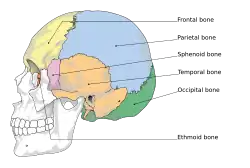

Lateral view of the human skull with the neurocranium highlighted.

The human skull is anatomically divided into two parts: the neurocranium, formed by eight cranial bones that houses and protect the brain—and the facial skeleton (viscerocranium) composed of fourteen bones, not including the three ossicles of the inner ear.[23] The term skull fracture typically means fractures to the neurocranium, while fractures of the facial portion of the skull are facial fractures, or if the jaw is fractured, a mandibular fracture.[24]

The eight cranial bones are separated by sutures : one frontal bone, two parietal bones, two temporal bones, one occipital bone, one sphenoid bone, and one ethmoid bone.[25]

The bones of the skull are in three layers: the hard compact layer of the external table (lamina externa), the diploë (a spongy layer of red bone marrow in the middle, and the compact layer of the inner table (Lamina interna).[26]

Skull thickness is variable, depending on location. Thus the traumatic impact required to cause a fracture depends on the impact site. The skull is thick at the glabella, the external occipital protuberance, the mastoid processes, and the external angular process of the frontal bone. Areas of the skull that are covered with muscle have no underlying diploë formation between the internal and external lamina, which results in thin bone more susceptible to fractures.

Skull fractures occur more easily at the thin squamous temporal and parietal bones, the sphenoid sinus, the foramen magnum (the opening at the base of the skull that the spinal cord passes through), the petrous temporal ridge, and the inner portions of the sphenoid wings at the base of the skull. The middle cranial fossa, a depression at the base of the cranial cavity forms the thinnest part of the skull and is thus the weakest part. This area of the cranial floor is weakened further by the presence of multiple foramina; as a result this section is at higher risk for basilar skull fractures to occur. Other areas more susceptible to fractures are the cribriform plate, the roof of orbits in the anterior cranial fossa, and the areas between the mastoid and dural sinuses in the posterior cranial fossa.[27]